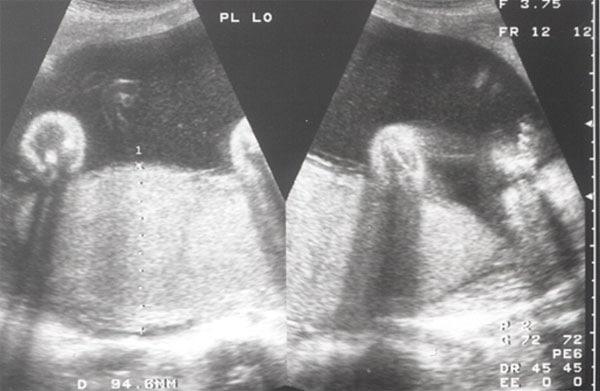

This course delves into the use of the Middle Cerebral Artery Doppler Peak Systolic Velocity (MCA-PSV) as a non-invasive method for assessing fetal anemia, particularly in isoimmunized pregnancies. The MCA-PSV measurement is highly reliable and allows clinicians to detect severe anemia in fetuses early, reducing the need for invasive procedures like amniocentesis or percutaneous umbilical blood sampling.

List the technique to obtain the peak systolic velocity of the middle cerebral artery and the etiology of increased velocities.

Apply the measurement peak systolic velocity of the middle cerebral artery to manage the fetus with suspected anemia.